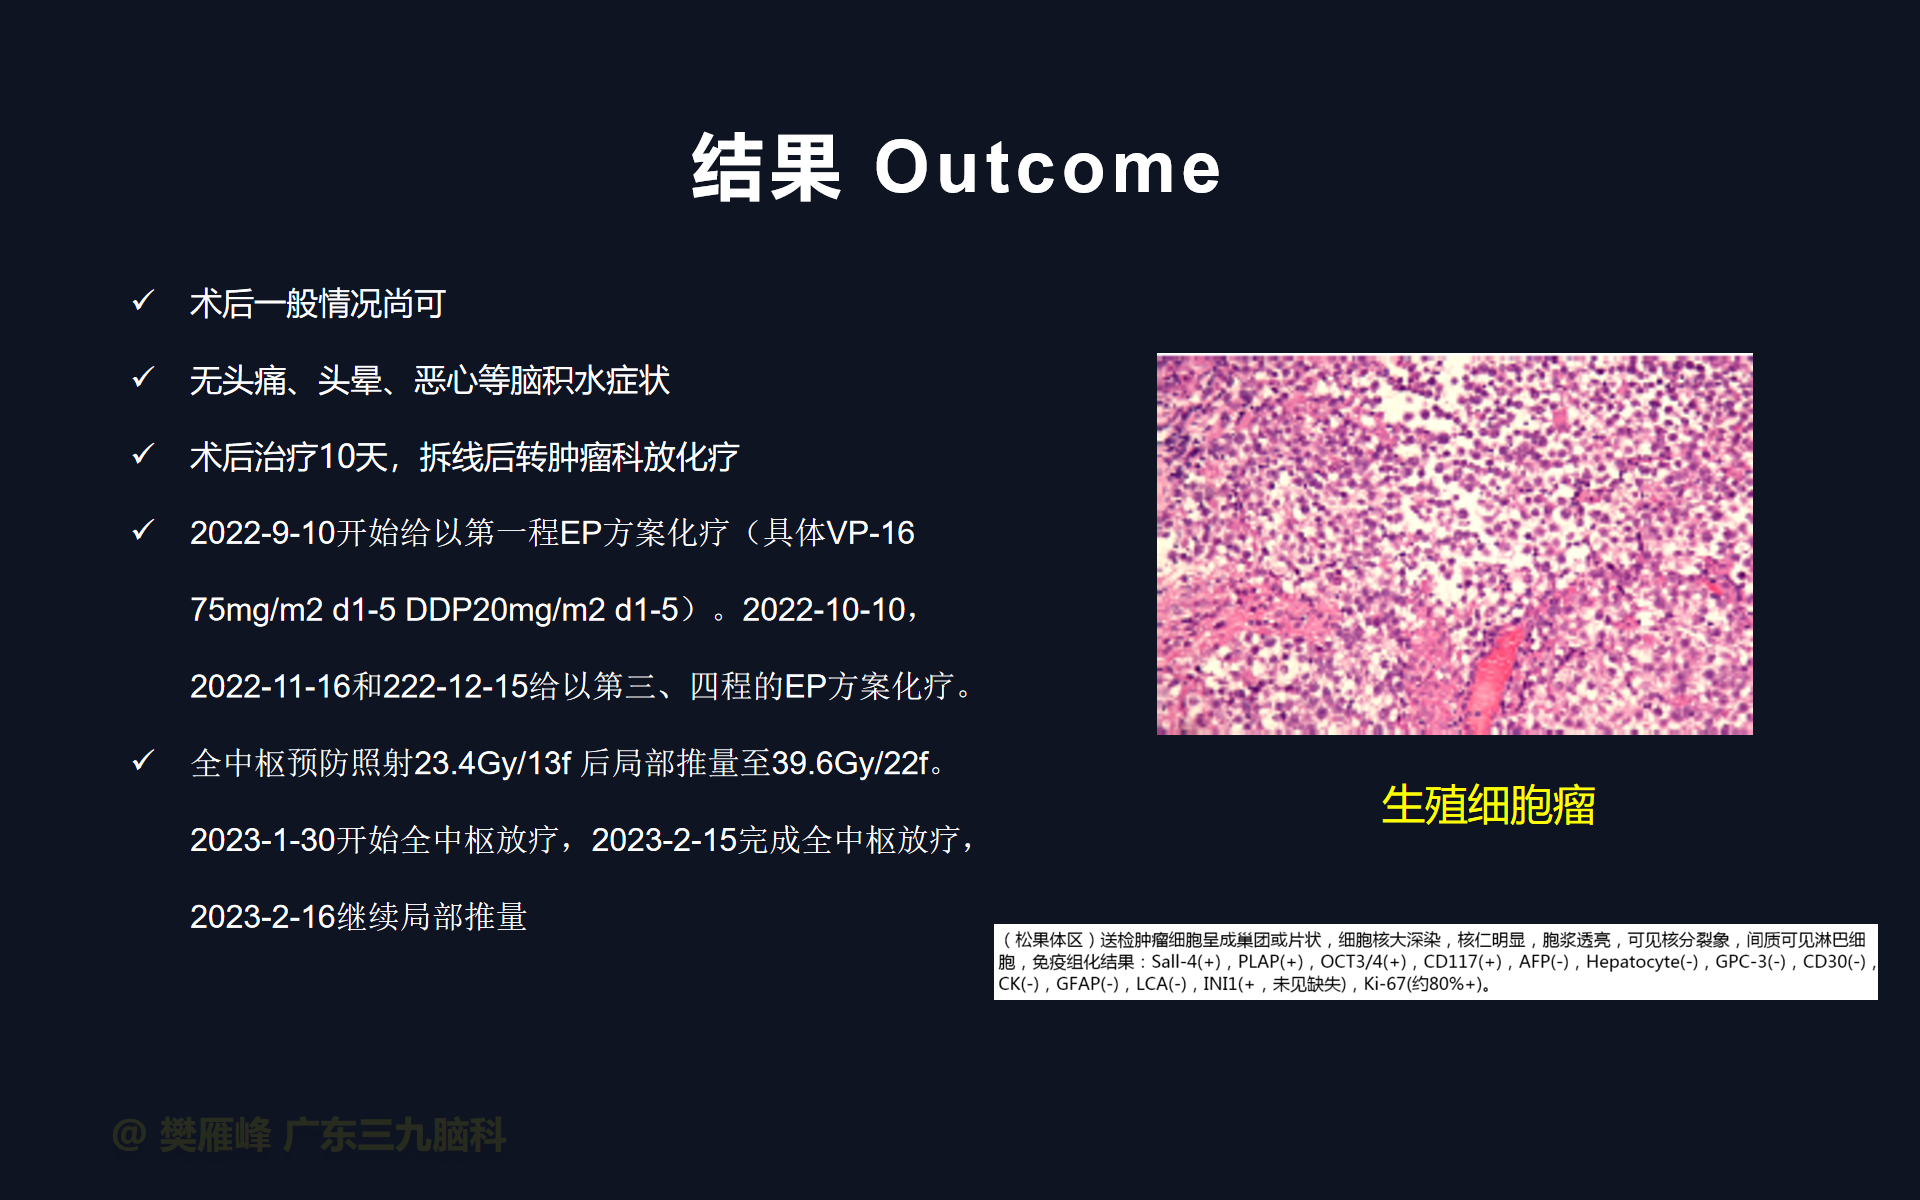

在这个二维手术视频中,展示了2例神经内镜下三脑室底造瘘+活检治疗三脑室后部肿瘤的方法。患者均为三脑室后部病变导致的梗阻性脑积水,病理结果1例为生殖细胞瘤,1例为淋巴瘤,在经过术后的放化疗病情均得到控制,生活质量满意。我们展示了安全的病变活检和第三脑室造瘘的技术要点,以最大限度减少术后继发脑积水和早期并发症。